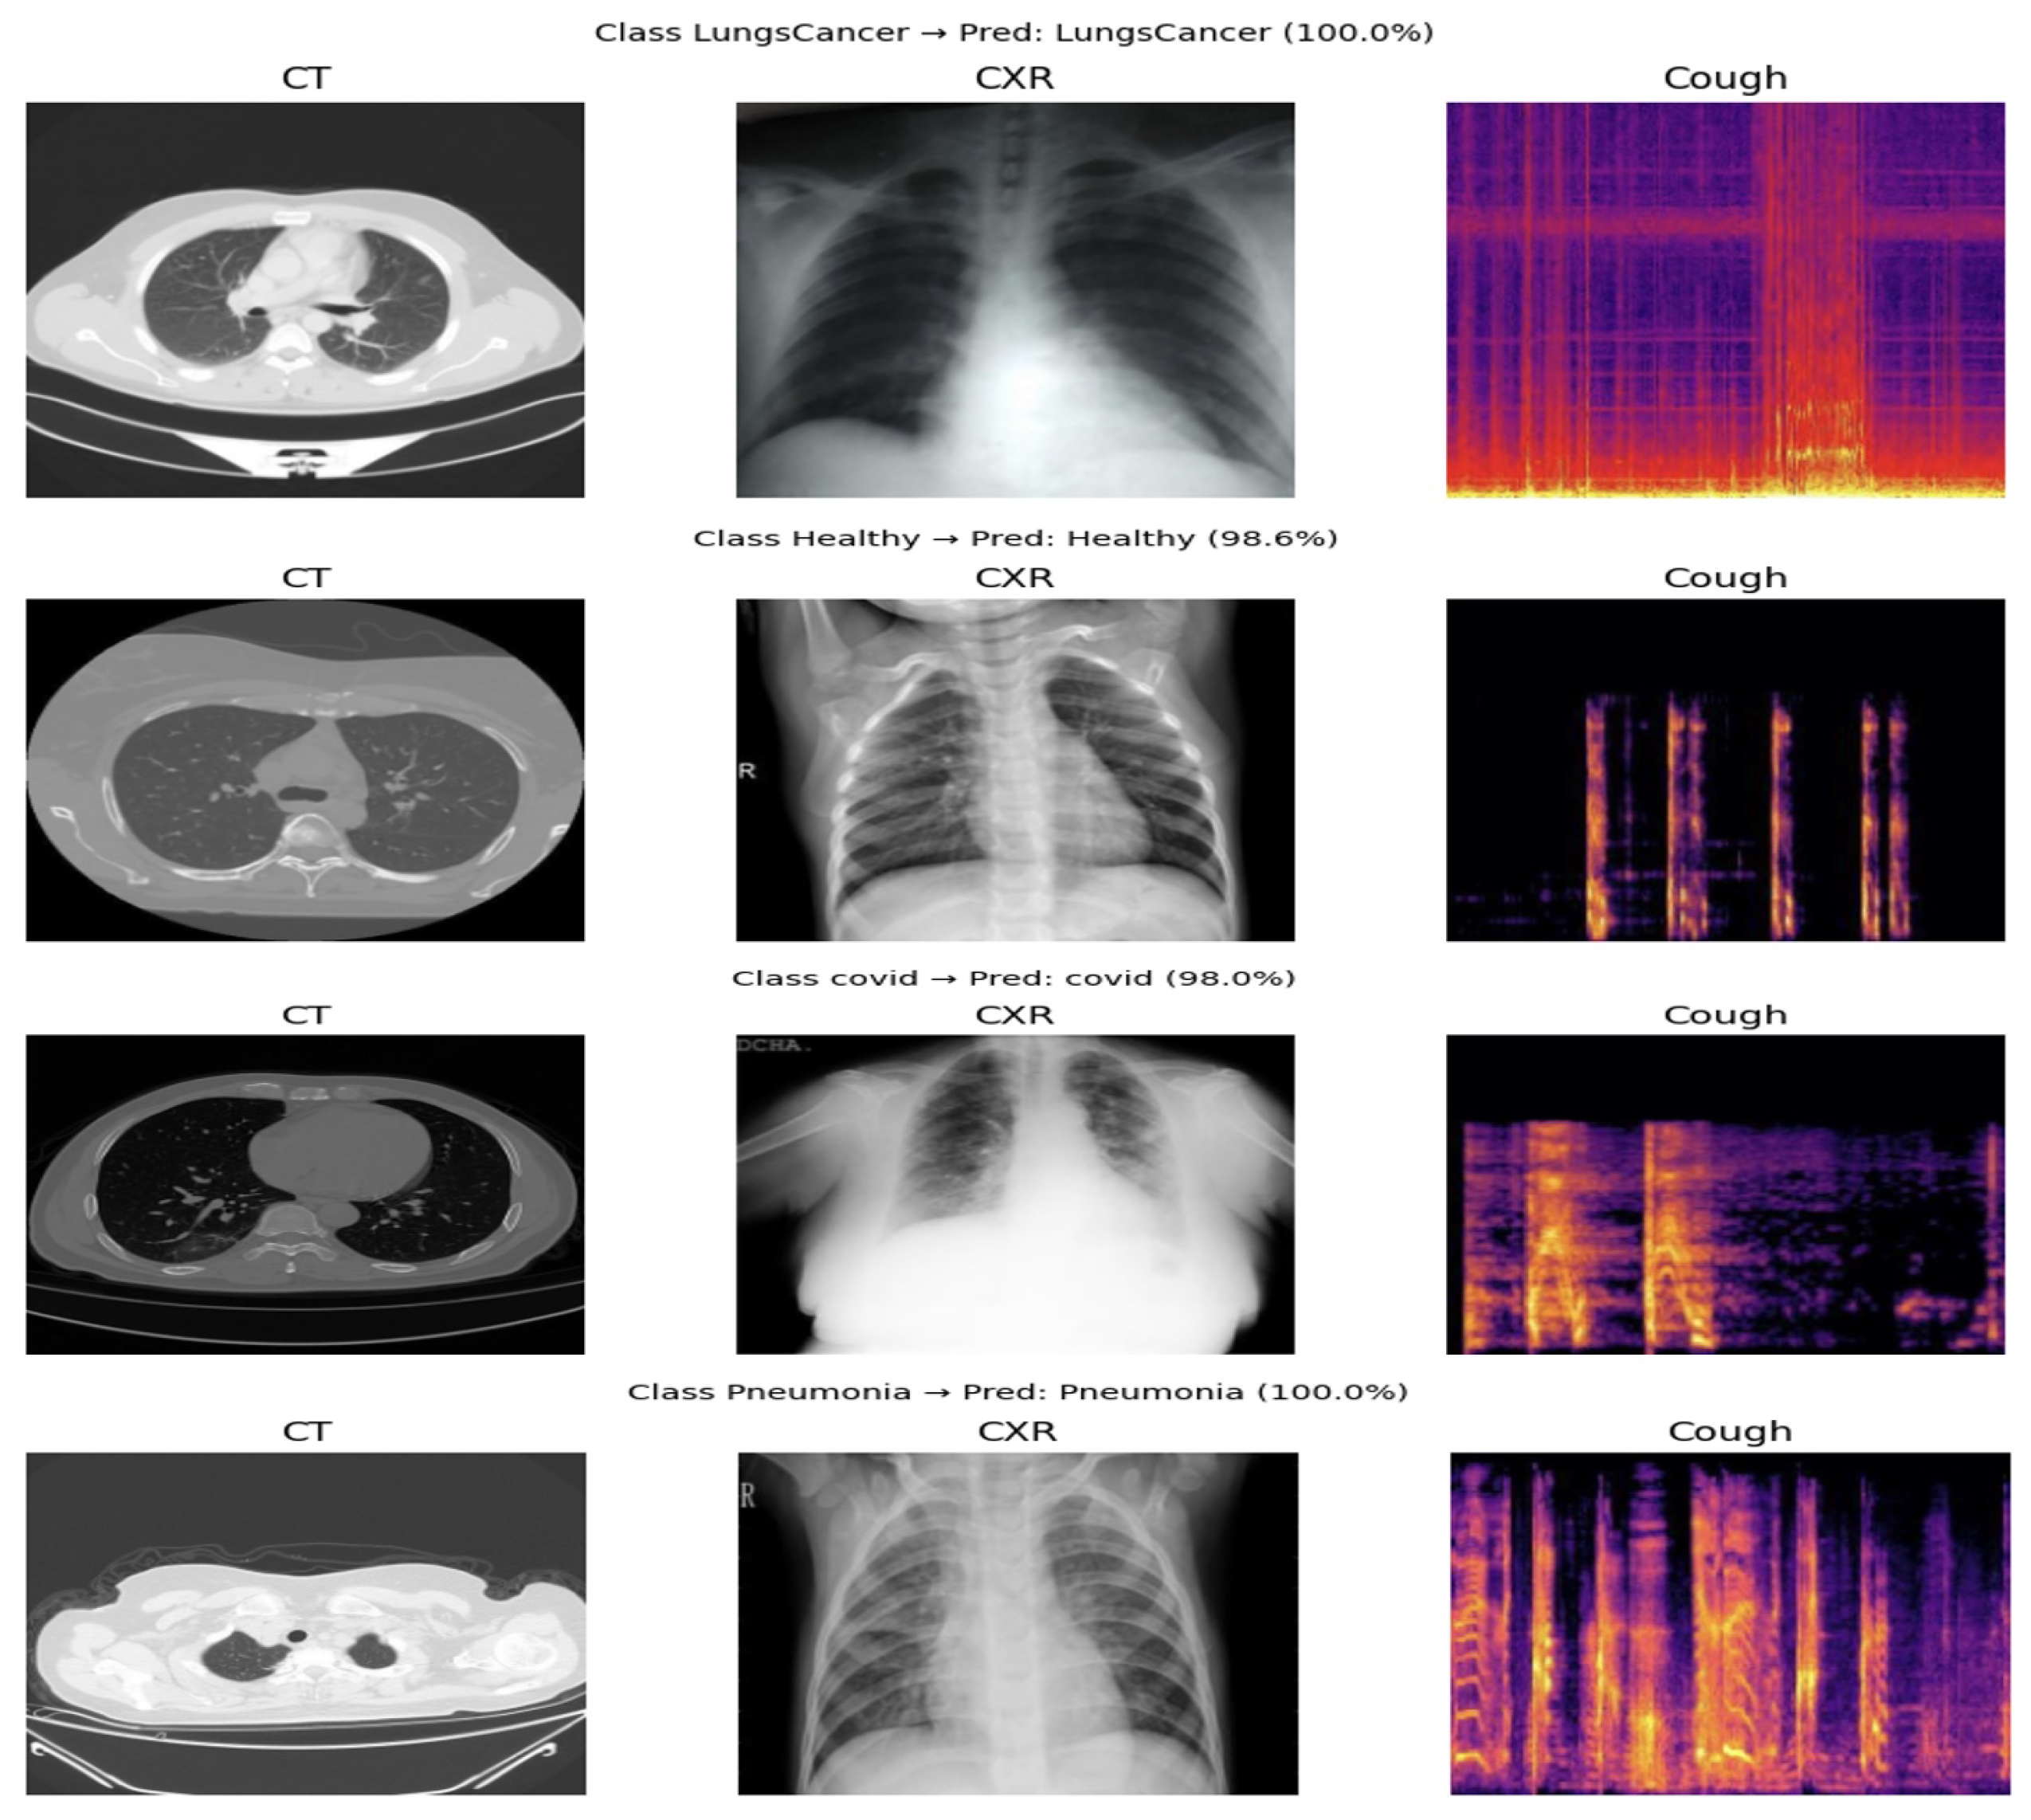

- Tri-modal data construction: In this study, a tri-modal instance was constructed by associating the chest X-ray images, CT scan images, and cough sound samples that shared the same disease label. Due to the absence of patient-level identifiers across the publicly available datasets, strict patient-level pairing across modalities was not feasible. Therefore, each tri-modal sample was formed through label-based alignment, where one sample from each modality corresponding to the same disease class was grouped to create a single training instance.This strategy enables the model to learn complementary representations across heterogeneous modalities while maintaining consistent diagnostic labels. The resulting framework captures cross-modal correlations at the label level rather than at the individual patient level. This design choice reflects a practical scenario in which different diagnostic tests may be independently available but still jointly contribute to clinical decision making.